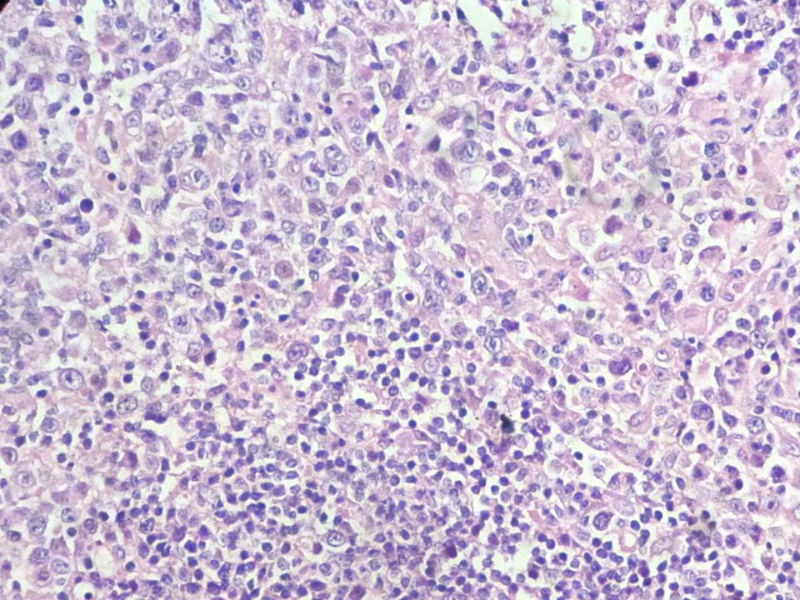

该患者可能存在病毒的感染,抑或是EB病毒的感染,包括CD30+的细胞在内,夹杂在组织细胞、小淋巴细胞之间的一些个大细胞是活化的淋巴细胞,表型看来属B细胞。整个形态呈反应性增生的形态。

请看下图,显示的细胞比较杂,胞浆较丰富,胞核没有什么特别的异型性。没有促纤维增生反应和围血管生长表现,没有肿瘤性坏死,没有见到更多的核分裂,特别是病理性核分裂。因此认为,本例是淋巴组织反应性增生,可能是对病毒感染的反应。